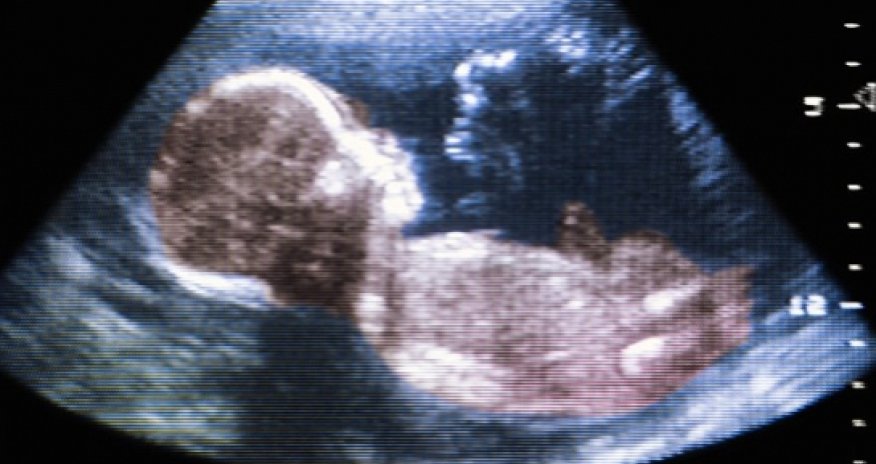

Toxins in the environment have been revealed in a new study to possibly cause autism.

A team of researchers from the University of Chicago concluded that exposure to toxins such as pesticides while in the womb can lead to a significantly greater risk of developing the disorder.The findings published this week in the PLOS Computational Biology Journal were culled from health records of over 100 million Americans in an effort to shift research from almost exclusively genetic to include environmental factors.Essentially what happens is during pregnancy there are certain sensitive periods where the fetus is very vulnerable to a range of small molecules – from things like plasticizers, prescription drugs, environmental pesticides and other things,’ study author Andrey Rzhetsky told Fox News.‘Some of these small molecules essentially alter normal development,’ the University of Chicago professor of genetic medicine and human genetics continued. ‘It’s not really well known why, but it’s an experimental observation.’The defects were especially noticeable in boys’ reproductive systems, Rzhetsky noted.Rates were compared against those reproductive system defects and the findings were alarming – instances of autism rose 283 per cent against every one per cent rise in outnumbered congenital malformations such as micropenis, Fox News reported, citing the study.Other intellectual disabilities increased by 94 per cent for ever one per cent increase in malformations, findings showed.‘Malformations predict very strongly the rates of autism, and the rate of malformation per person varies significantly across the country,’ Rzhetsky told Fox. ‘Some counties have low rates and some have very high.  And rate of malformations is higher in counties with higher rates of autism.’Instances were much higher in young males, but females were affected to – just not as highly.One in 88 children suffers from autism, and diagnoses in boys greatly outnumber those in girls, according to the Centers for Disease Control and Prevention. No clear cause has been established for the disorder.‘The environment may play a very significant role in autism, and we should be paying more attention to it,’ said Rzhetsky. ‘We should definitely take into account environmental factors.’(dailymail.co.uk)ANN.Az